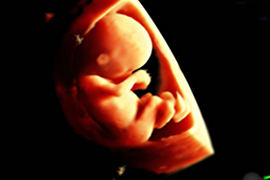

Im zweiten Drittel der Schwangerschaft wächst das Kind und die Organe reifen weiter, um schließlich zum Zeitpunkt der Geburt ihre Funktion übernehmen zu können. Bei diesem Reifungsprozess verändert sich nur noch die mikroskopisch erkennbare Feinstruktur der meisten Organe. Die im Ultraschall darstellbaren typischen Organstrukturen sind jetzt schon vorhanden. Nur das Gehirn wird sich in den folgenden Wochen noch bedeutsam verändern.

Daher ist das zweite Drittel der Schwangerschaft ein geeigneter Zeitpunkt, eine differenzierte Ultraschallfeindiagnostik vorzunehmen. Das Kind schwimmt in reichlich Fruchtwasser – ein guter Schall-Leiter!

In der 20. Schwangerschaftswoche ist das kindliche Herz etwa so groß wie eine Himbeere – und trotzdem können wir bereits die Kammern und Herzklappen und die zu- und abführenden Blutgefäße darstellen!